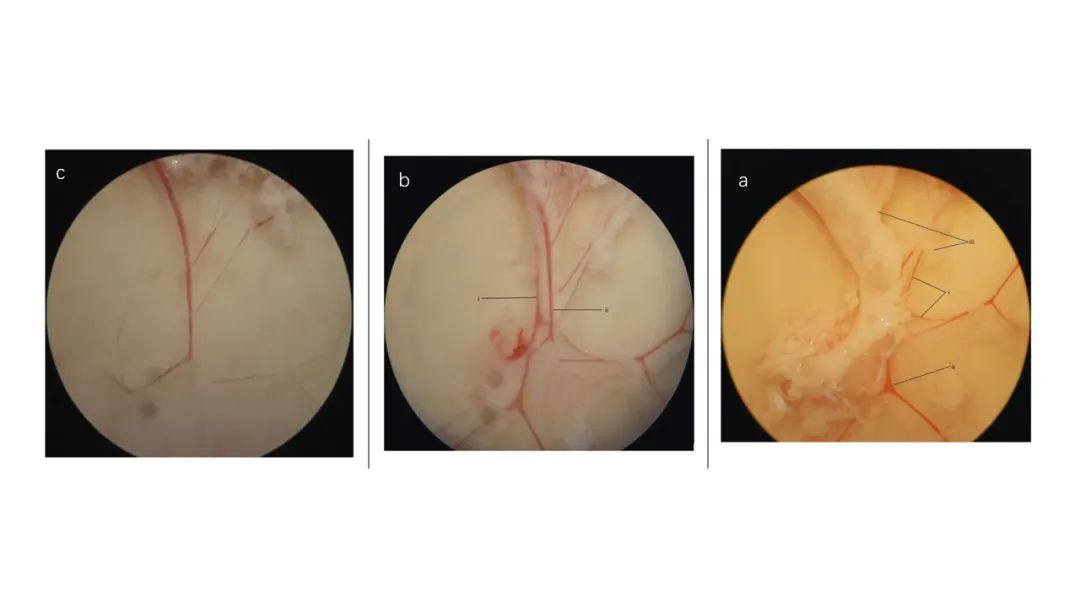

肠系膜血管解剖显微镜下图像。(a)去除结缔组织和神经束前,可见(i)动脉、(ii)静脉和(iii)粘附脂肪。(b)切除大部分结缔组织和神经束后。(i)位于(ii)静脉下方的动脉比后者显得“更白”。(c)清洁的动脉。